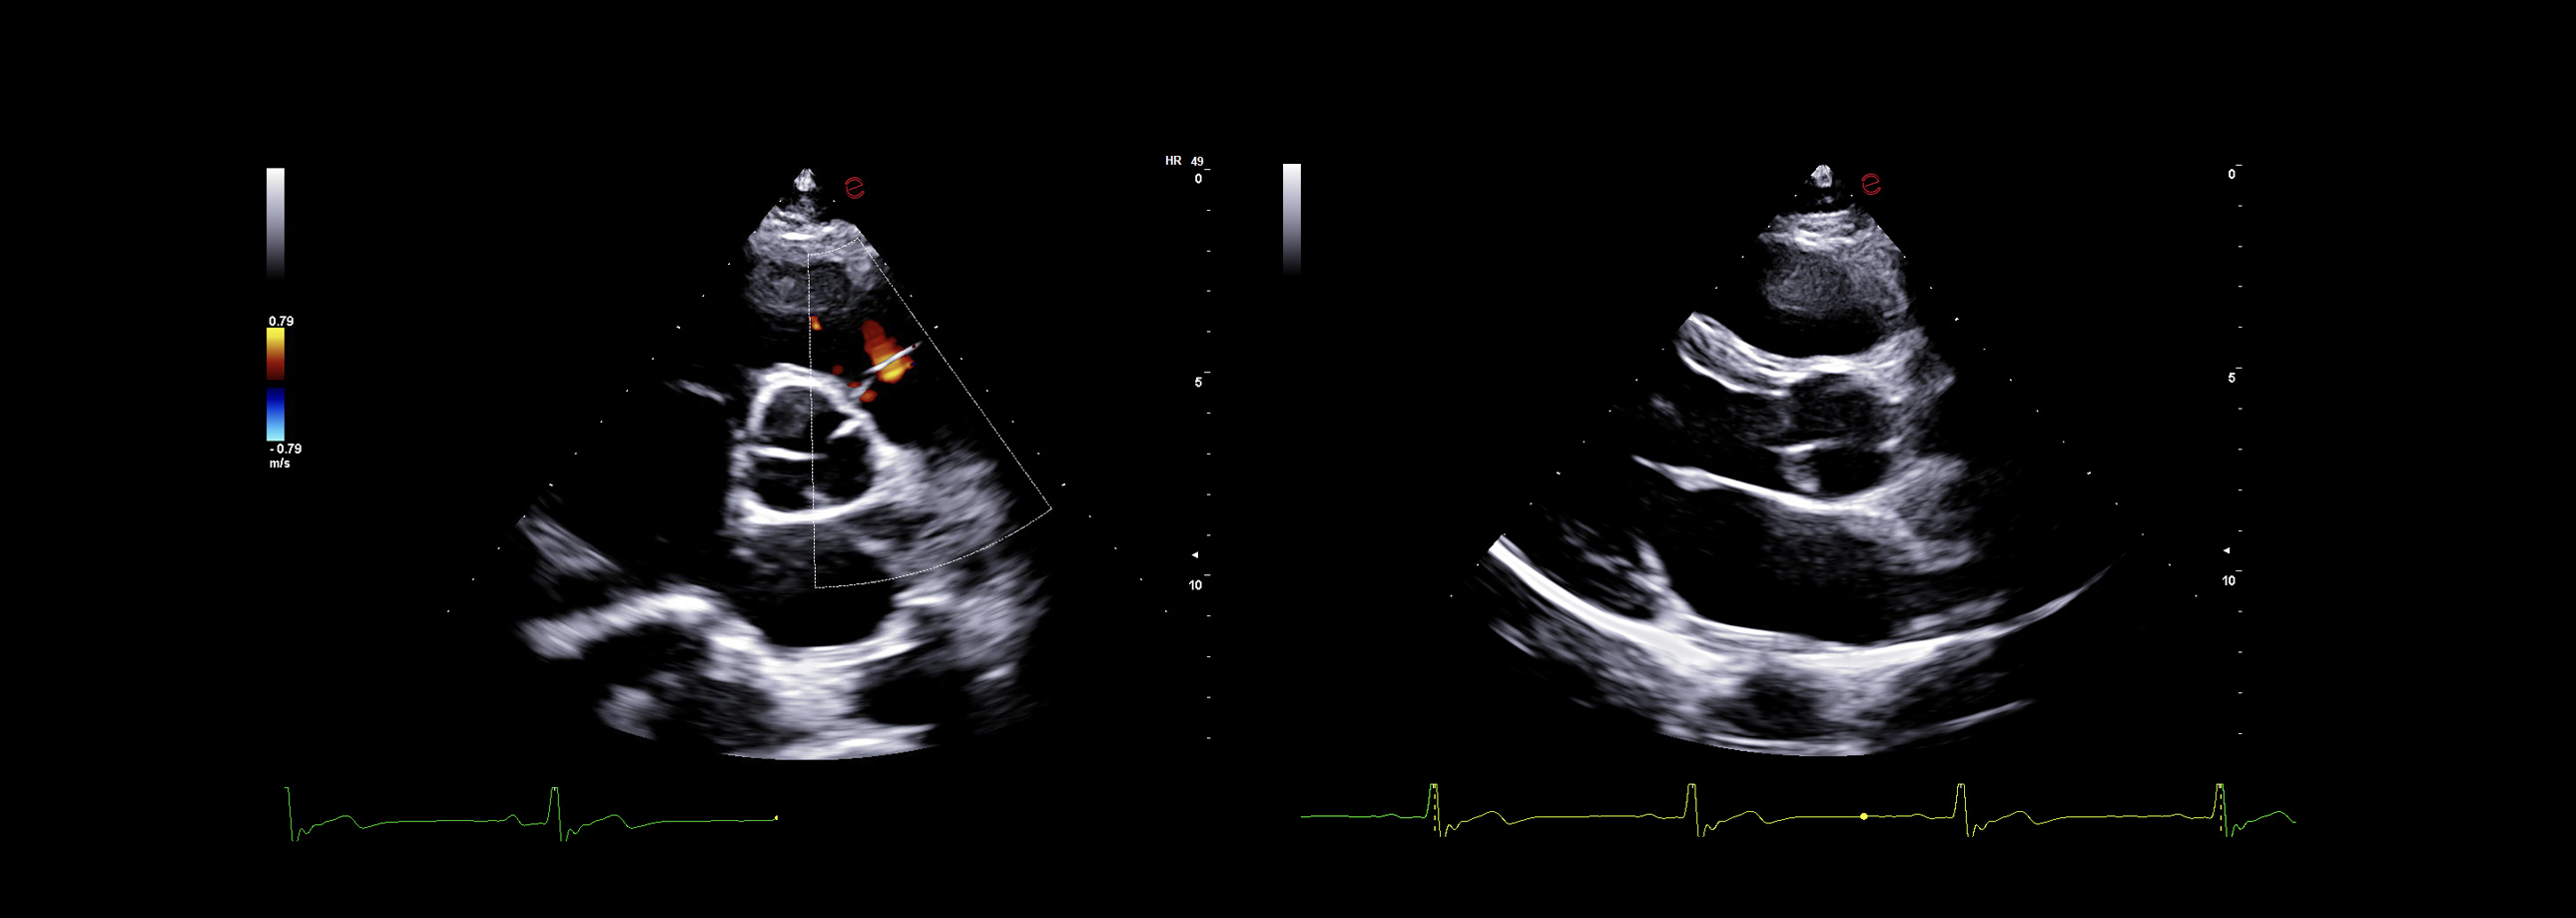

Esaote’s XCrystal probe PX1-5 delivers exceptional clarity in B-mode imaging, providing deep penetration and excellent resolution even in technically challenging patients. Its advanced architecture ensures high Doppler sensitivity and spatial detail, enabling an accurate assessment of wall motion, valve morphology, and flow dynamics. From subtle endocardial borders to low-velocity diastolic flows, the PX1-5 probe ensures you never miss the details that matter.

AI-based cardiac measurements for speed and consistency

Esaote’s AutoEF and AutoCM tools are designed to bring a step ahead in the device use experience. With advanced AI algorithms, AutoEF automatically recognizes apical views and traces endocardial borders offering a proposal of left ventricular volumes and ejection fraction in just seconds. AutoCM complements this by automatically suggesting ventricular wall thickness, internal diameters, and derived values such as LV mass and fractional shortening directly from parasternal views. Moreover, AutoCM assists cardiologists by automatically recommending a calculation of the E/A wave ratio of the mitral valve, providing crucial information on diastolic function.

Together, these tools help clinicians to obtain accurate, guideline-aligned measurements in a fast way, enhancing diagnostic reliability. AutoEF and AutoCM automate key functional and structural measurements—such as ejection fraction, LV volumes, wall thickness, and LV mass— making a smooth workflow, especially in high-throughput clinics.